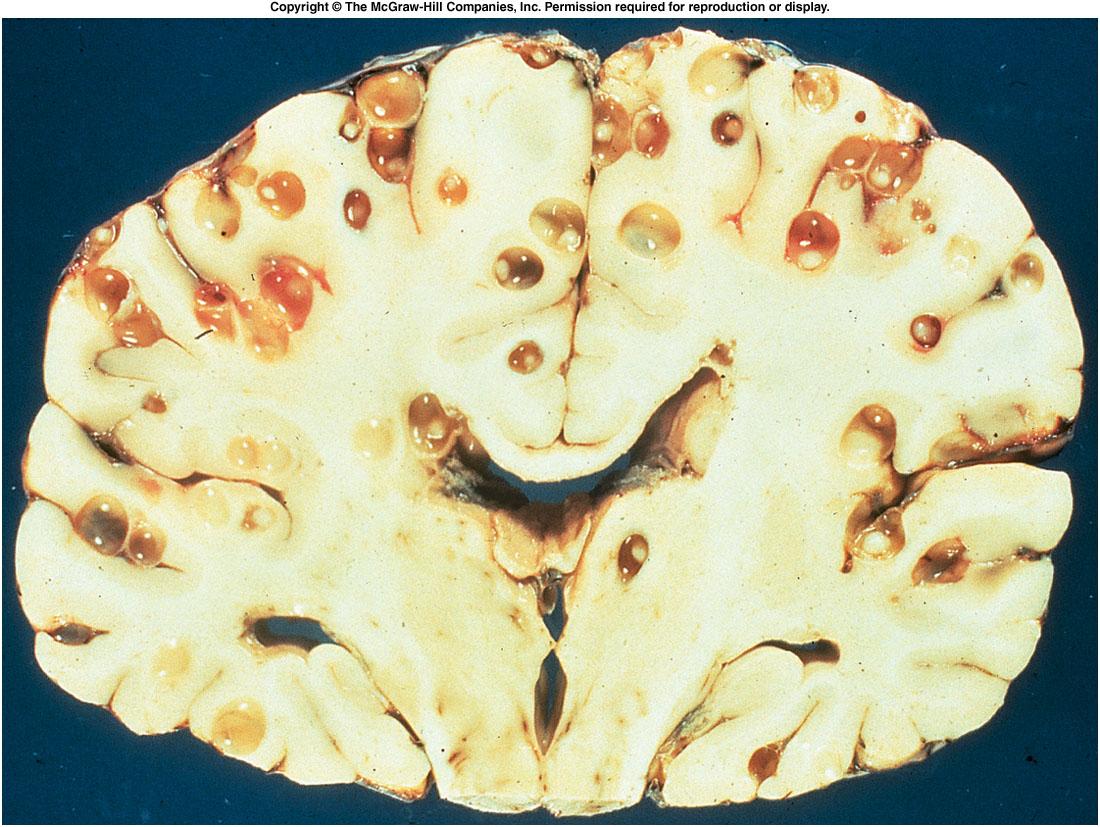

La neurocisticercosis es la más importante localización de la cisticercosis. Los cisticercos se pueden localizar en muchas partes del organismo, pero en la mayoría de los casos comprometen el SNC. Después de esta localizacion le siguen en frecuencia, el tejido celular subcutáneo y los ojos. El número de vesículas puede ser múltiple, aunque en ocasiones se observan muy pocas o sólo una. En el SNC puede invadir cualquiera de sus estructuras. La localizacion más frecuente es en el parénquima de los hemisferios  cerebrales, seguido de las cavidades ventriculocisternales principalmente el IV ventrículo, espacio subaracnoideo, las meninges y la médula.

La cisticercosis múltiple es más frecuente que la única. La forma racemosa prefiere las cavidades, en las cuales adquiere diferente forma y tamaño. La inflamación de los tejidos, principalmente en SNC, se presenta con mayor intensidad cuando los quistes mueren, bien sea espontáneamente o por tratamiento. En estos casos, en la vecindad de los cisticercos se presenta una reacción inmunológica con exudado, inflamación, periarteritis y endarteritis, que puede obliterar la luz de los vasos, obstruir los conductos del LCR y causar hipertensión intracraneana e hidrocefalia.

En algunas localizaciones produce lesiones en los pares craneanos. La meningitis por cisticercosis produce engrosamiento de las membranas y abundante exudado. Si está comprometida la aracnoides, se pueden afectar los pares craneanos de la base y contribuye a la obstrucción del LCR. La invasión de la médula espinal es poco frecuente. Se ha descrito una forma miliar con múltiples cisticercos pequeños que se localizan principalmente en el parénquima cerebral, en cuyo caso se produce encefalitis. Debido a la gran inflamación difusa, es posible que no se observen los quistes en la escanografía.

En cuanto a la localización dentro del SNC, se ha encontrado que aproximadamente la mitad están en los hemisferios, una tercera parte en las cisternas, una cuarta parte en los ventrículos y aproximadamente 5% en la médula espinal. Las lesiones múltiples son dos veces más comunes que las únicas en los hemisferios y cisternas, mientras que en los ventrículos es más frecuente la presencia de quistes únicos. Excepto en el cerebro y en el ojo, los cisticercos vivos están rodeados por una cápsula fibrosa, fácilmente desprendible del tejido que los rodea.

Mientras estén vivos presentan mecanismos de adaptación al huésped que les permite una vida muy larga, hasta más de 20 años, y poca reacción inflamatoria periquística. Al morir se degeneran en una masa amorfa, rodeada de células gigantes, histiocitos, células epitelioides, linfocitos y eosinófilos, que progresivamente se va fibrosando y termina por calcificarse. Como el promedio de vida de los quistes es muy variable, lo más frecuente es encontrar en el mismo paciente, cisticercos vivos, en vía de destrucción y calcificaciones.